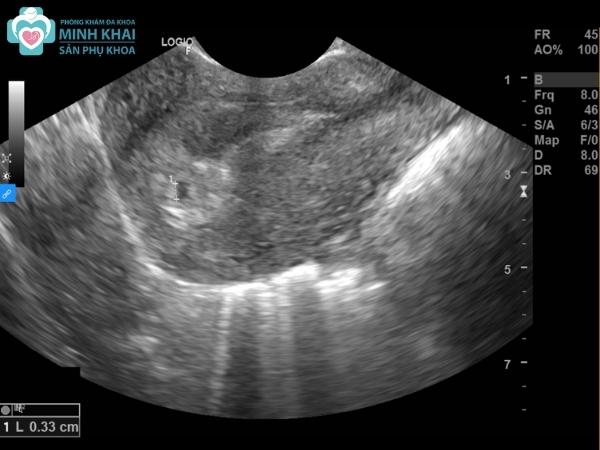

Trước tiên để trả lời được câu hỏi có nên siêu âm thai nhiều không cần nắm rõ được cơ chế hoạt động của chúng. Phương pháp siêu âm thai nhi là kỹ thuật sử dụng máy dò phát sóng âm với tần số cao áp trực tiếp lên thành bụng người mẹ.

Chúng cho phép thu lại những hình ảnh, đoạn phim ngắn bên trong cơ thể một cách chân thực. Các thông số, tình trạng của thai nhi cũng được xác định khá rõ ràng thông qua cách khám thai này. Từ đó bác sĩ có thể chẩn đoán được những đặc điểm của bào thai về hình thái, kích thước, số tuổi,... cũng như phát hiện các dị tật bẩm sinh.